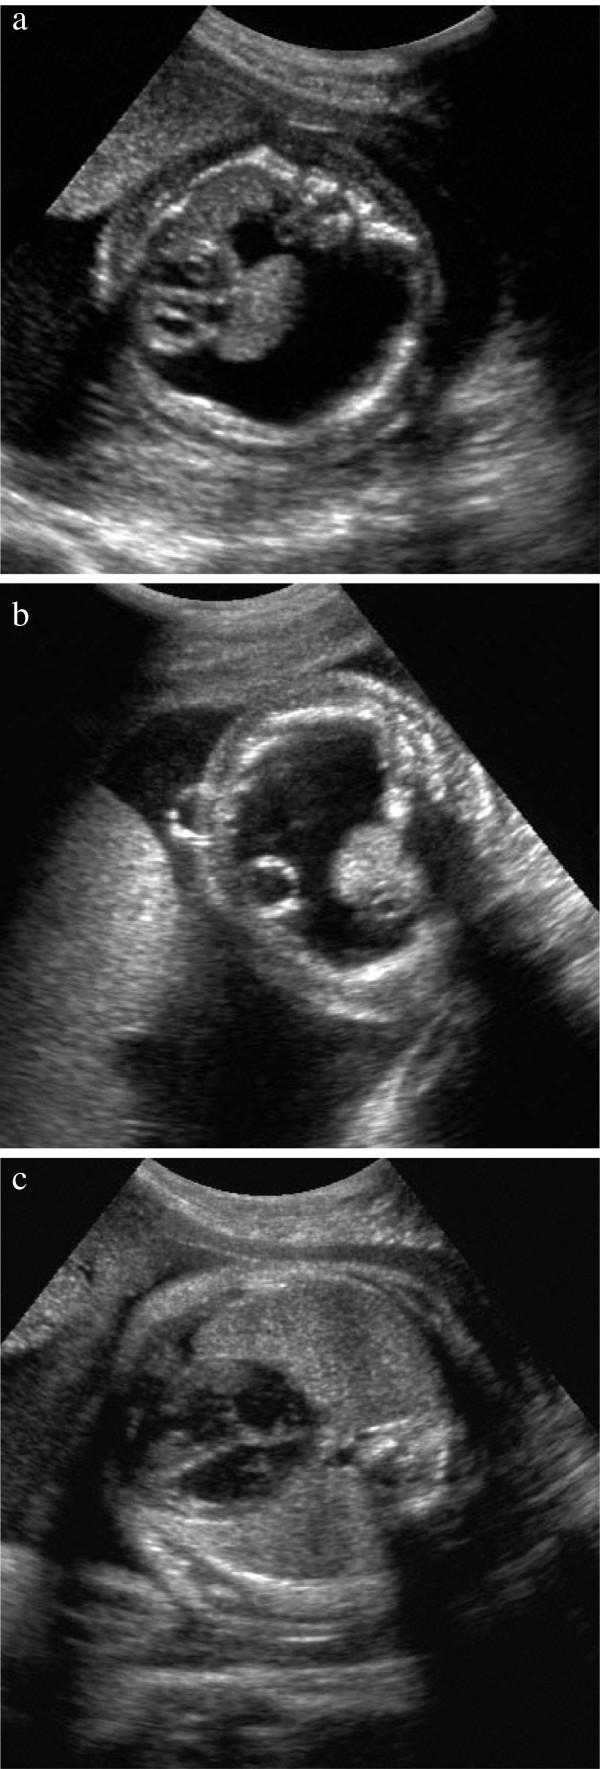

We report four cases with transient hydrops fetalis resulting from LSD and performed a literature review on LSD with NIHF and congenital ascites in combination.

At present, 12 different LSDs are described to be associated with NIHF or congenital ascites. Most patients had a family history of NIHF, where the preceding sibling had not been examined. A diagnostic approach to the fetus with NIHF due to suspected LSD either in utero or postnatal is suggested. Transient forms of NIHF and/or ascites in association with MPS IVA, MPS VII and NPC are described for the first time in this publication.